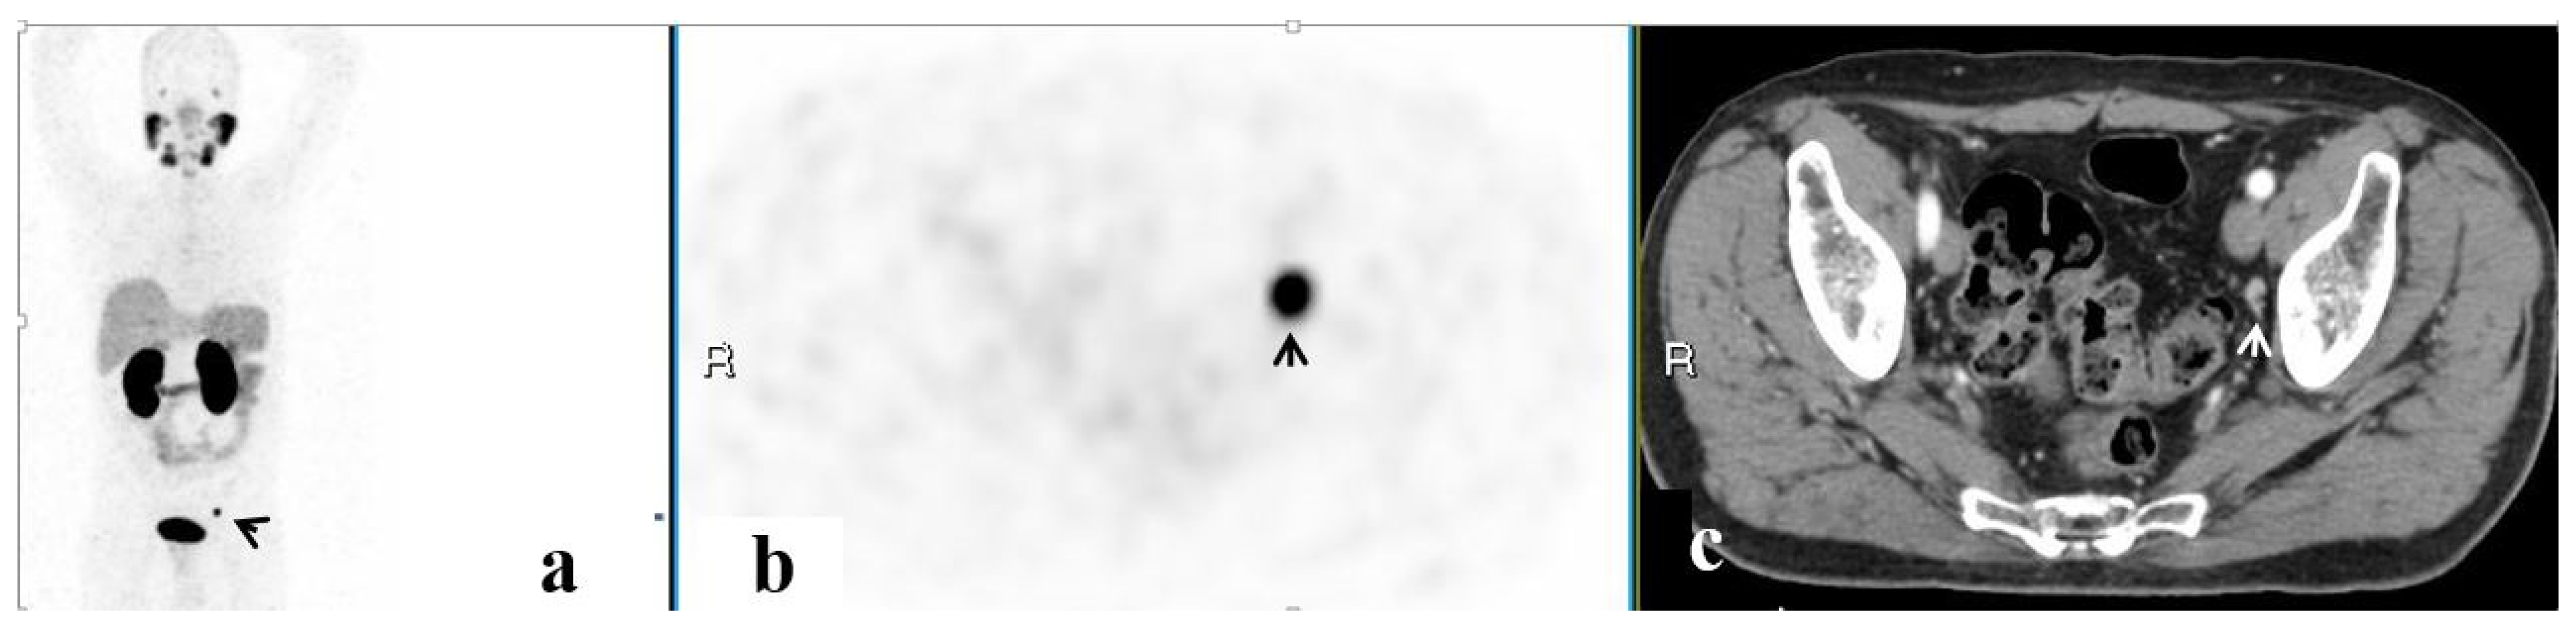

| Site | No. of Men | Mean SUVmax 1 | Mean Lesion Size (mm) 1 | No. Accompanied by LN |

|---|---|---|---|---|

| Isolated pelvic LAD | 43 | 11.0 ± 11.5 | 1.0 ± 0.3 | n/a |

| Prostate | 37 | 10.0 ± 6.4 | 2.1 ± 1.1 | 11 |

| SV | 23 | 8.6 ± 5.9 | 0.5 ± 0.5 | 7 |

| Pelvic bones | 16 | 14.2 ± 18.2 | 2.0 ± 1.0 | 2 |

| PF | 7 | 5.8 ± 5.6 | 1.4 ± 0.4 | 2 |

| SVF | 3 | 6.0 ± 1.6 | 1.3 ± 0.4 | 1 |

| Other 2 | 6 | 8.0 ± 3.2 | 1.3 ± 0.4 | 2 |